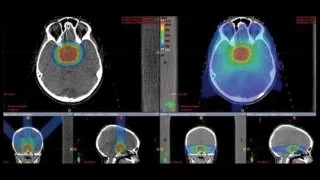

如果位于覆盖大脑的膜内或切除不会损害周围区域的区域,手术是脑肿瘤的主要治疗方法。位于敏感区域内或附近的脑瘤会使全切除术更具风险,有时甚至是不可能的。由于质子束的准确性,质子治疗在脑深处或敏感区域附近的肿瘤中特别有用。

质子治疗是一种被证实为合适而顺利的放疗手段,相比传统放疗,质子治疗可以在杀伤肿瘤的同时减少对正常细胞的影响。那么质子治疗究竟好在哪里?疗程怎样?效果如何?INC国际神经外科在这里解析脑瘤质子治疗的十问十答,建议收藏!

当质子穿过人体时,它们与电子相互作用并释放能量,同时减速,找出并释放出较高能量的点称为“布拉格峰”,就相当于“定点爆破”。在这一点上,几乎全部剩余的质子都被吸收了。超出范围的健康组织几乎不会受到辐射。另外,相对较大的质子质量意味着在邻接的健康组织中几乎没有侧面散射。

然而,质子在到达肿瘤的途中确实向健康组织沉积了放射线,尽管(与X射线相反)质子的剂量比目标肿瘤细胞所接受的剂量低。